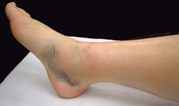

初診時の写真・X線

スライドの写真は初診時の外観で内出血の様子